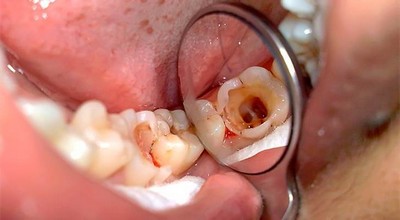

Микроорганизмы начинают выделять кислоту, остатки пищи разлагаются, и зубная эмаль постепенно разрушается. Образуется кариес, инфекция которого с течением времени проникает в дентин (костное вещество зуба), а затем и в пульпу. В этой мягкой ткани расположено огромное количество нервных окончаний. Отёкшая воспалённая пульпа их сдавливает, что вызывает острую пронизывающую боль.

Для острого воспаления характерен отёк пульпы, появление диффузных, гистиоцитарных или круглоклеточных инфильтратов. Ондобласты дезорганизуются, снижается количество гликогена.

В увеличенных клетках отсутствуют липиды, рибосомы, гранулы гликогена. Наблюдается множество базофильных клеток, клеточная очаговая пролиферация, прогрессивно образуются макрофаги, а по ходу сосудов происходит полиморфно-клеточная инфильтрация.

Периодически встречается диапедез эритроцитов с мелкими очагами кровоизлияний. В нервных волокнах заметны незначительные дистрофические изменения. Это продолжается несколько часов, после чего происходит миграция нейтрофилов с массовыми скоплениями вокруг венул. Дистрофические изменения прогрессируют, и распадается миелин. Это является началом диффузного гнойного пульпита.